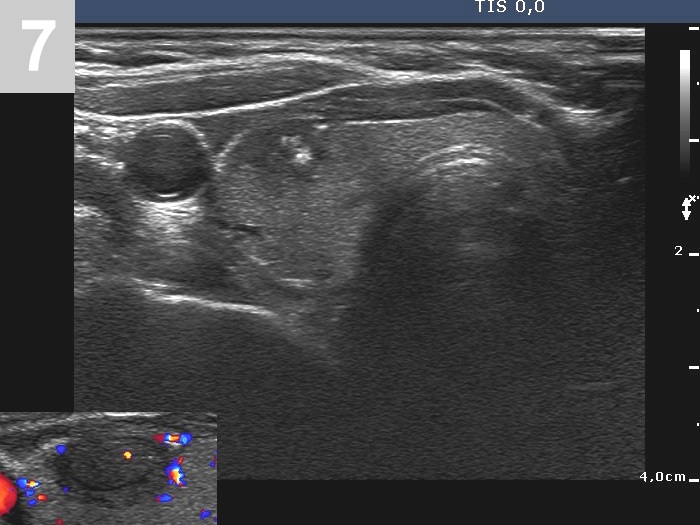

3 US of thyroid cancer

Pre- and postoperative ultrasound in thyroid cancers

Cases to be discussed on January 18, 2024